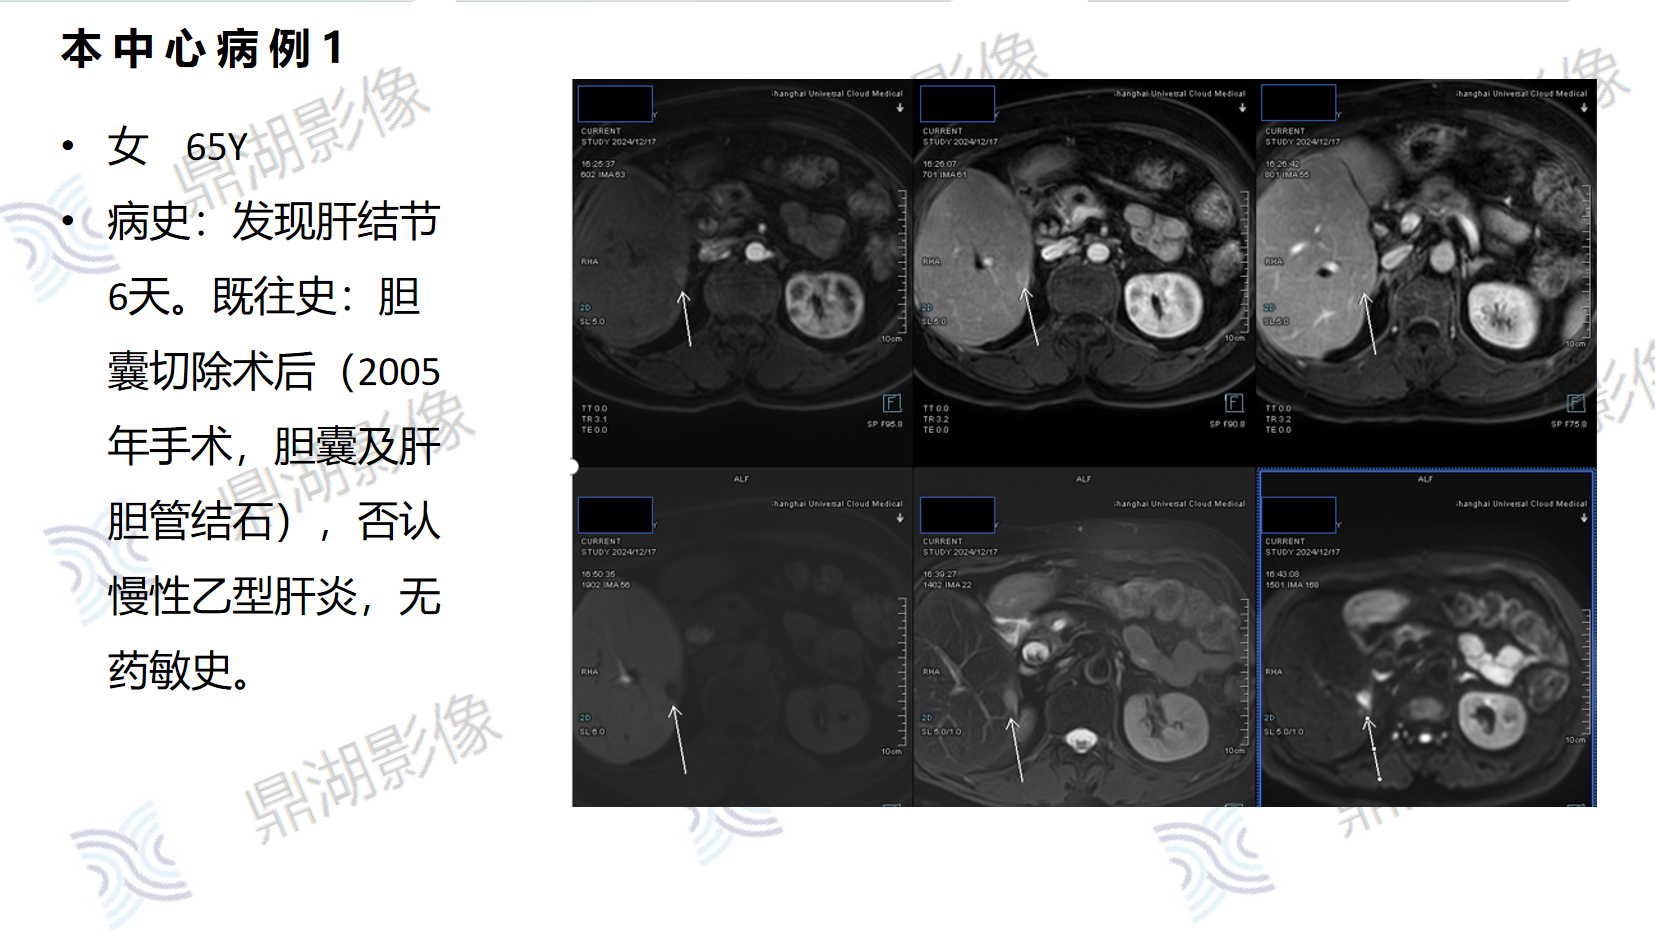

性别:女

年龄:32

主诉:B超肝实质回声细密增强,MRI提示肝左外叶结节,考虑恶性可能